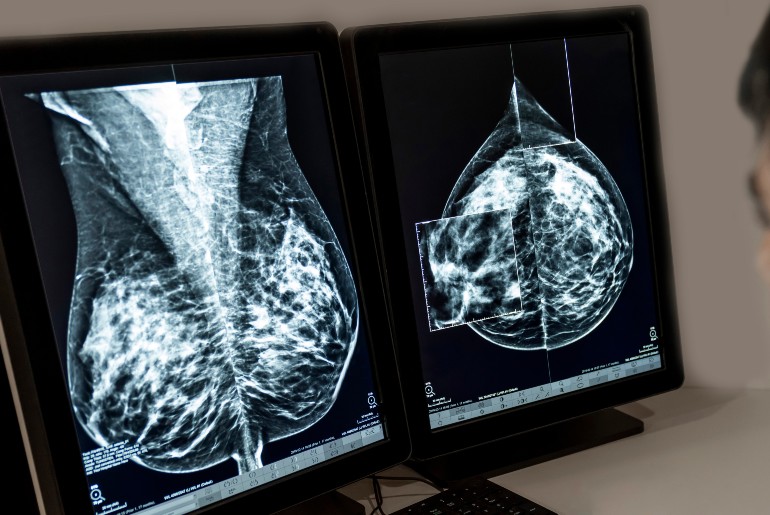

Brustkrebs-Früherkennung: MRT und Kontrastmittel-Mammographie entdecken mehr Tumore als Ultraschall

Risikoadaptierte Krebsfrüherkennung bei Mammographie-Screening